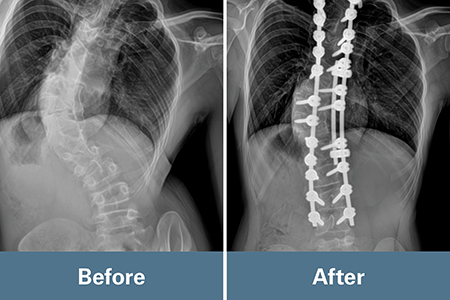

Kai’s curve had grown from 40 degrees preadolescent to 70 degrees when Borden first saw Kai as a 13-year-old in 2021. Borden recommended they continue to closely monitor Kai’s spine growth to allow time for his lungs to develop without rods and screws in the spine. He didn’t want to move too quickly into surgery, unless necessary. For two years, Kai visited Borden every four months. His curve was slowly progressing.

When Kai’s spine curved 89 degrees, Borden decided that even though he was still growing, it was time to schedule spinal surgery to stop the progression of his curve and provide a balanced and corrected spine.

Kai’s surgery in August 2023 required inserting rods into the spine and securing them with screws. Kai’s anatomy was different, however. It was challenging to place the screws in the small channel of bones, called pedicles, because they weren’t in the typical anatomic location. As a result, they used interoperative CT scan and navigation to determine where to place the screws.

Kai’s results after surgery exceeded the team’s expectations regarding the correction of his spine, which measured 20 degrees. Today, his spine has fused, and the rods and screws are set and reinforced by his own bone now. He can sit without pain.